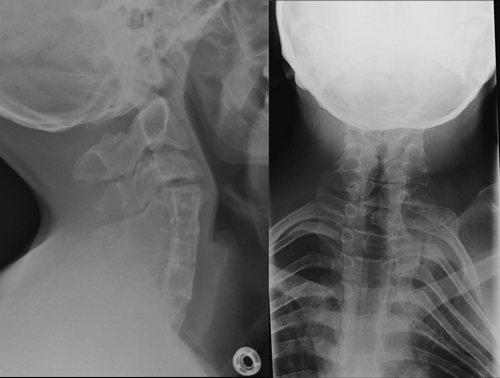

Рентгенологическим признаком данного заболевания является синостоз позвонков. Снимки следует делать в двух проекциях, чтобы избежать затенения важных деталей из-за необычного положения головы. Также необходимо выполнить рентгенографию с максимальным сгибанием и разгибанием шеи, а также сделать снимки грудного и поясничного отделов позвоночника для выявления возможных искривлений.